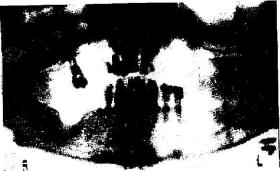

4. Лечите ли вы каверны? (Правильный ответ — Да. Путем очищения). Каверны — это просто полости, оставшиеся в челюстях после неправильно удаленных зубов. Ранка, образовавшаяся после Удаления зуба, если она вычищена, заживает и заполняется костью. Обычно стоматологи не вычищают впадину в тканях или в кости. Инфицированная рана — обычный результат такого лечения. Эти раны никогда полностью не заживают. Спустя 30 лет после удаления зуба каверны так и остаются. Это форма остеомиелита, что подразумевает инфицирование кости.

Др. К.: Каверны можно увидеть на рентгенограммах (смотри рисунок), я часто видела остеомиелит, особенно в случаях рака. Обычно он начинается в костях челюстей из-за проблем с зубами. Он распространяется из челюстей на остальные части тела.

| Рис. 3 |

Вам необходимо сделать обзорную рентгенограмму верхней и| нижней челюсти. Обзорная рентгенограмма покажет вес, включая состояние челюсти и наличие полостей, Это поможет стоматологу] увидеть вколоченные зубы; осколки, оставшиеся после удаления; кусочки ртути, погруженные в кость, и глубокую инфекцию. На обзорной рентгенограмме также можно увидеть каверны.